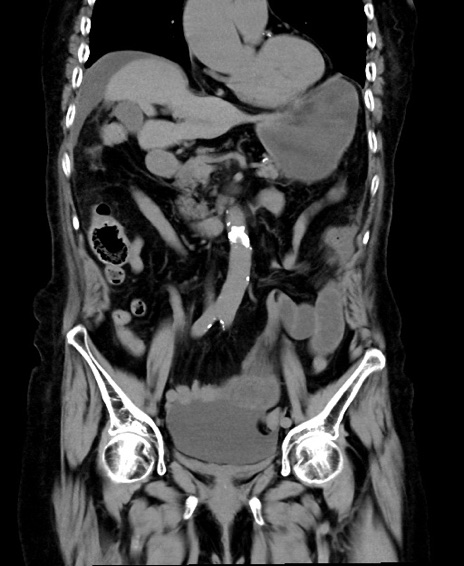

症例40(冠状断像)他院1日前

冠状断像